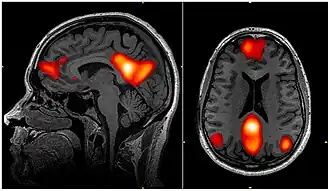

Als Default Mode Network (englisch DMN ‚Standard- oder Voreinstellungsmodusnetzwerk‘ bzw. sinngemäß ‚Ruhezustandsnetzwerk‘) bezeichnet man eine Gruppe von Gehirnregionen, die beim Nichtstun aktiv werden und beim Lösen von Aufgaben deaktiviert werden. Die Ruheaktivität dieser Hirnregionen lässt sich mit fMRT (v. a. Resting state fMRI), PET, EEG und MEG nachweisen.

Die Aktivität dieser Hirnregionen ist korreliert. Deshalb wird diese Gruppe von synchron aktiven Hirnregionen als Netzwerk aufgefasst. Das Netzwerk kann mit dem mathematischen Werkzeug Graphentheorie beschrieben werden. Zu den beteiligten Hirnregionen gehören z. B. der mediale präfrontale Cortex, Precuneus, Teile des Gyrus cinguli sowie – schwächer angebunden – der Lobulus parietalis superior des Scheitellappens und der Hippocampus. Die einzelnen Hirnstrukturen sind durch Weißesubstanzbahnen synaptisch miteinander verbunden.

Das Default Mode Network wurde 2001 von Marcus E. Raichle et al. beschrieben[13] Dabei wurden die aktivierten Gehirnareale im vermeintlichen Ruhezustand mit geschlossenen Augen oder ruhig auf einen Punkt fixiertem Blick mit denen verglichen, die während der Lösung von konkreten Aufgaben aktiviert waren. Es wurden Gebiete gefunden, die im Ruhezustand aktiver waren als bei der Konzentration. Nachdem man Fehldarstellungen ausgeschlossen hatten, wurde erkannt, dass das Gehirn Hintergrundaktivitäten zeigt, die im Ruhezustand vorherrschen, aber bei der Konzentration auf konkrete Funktionen heruntergefahren werden.[14]